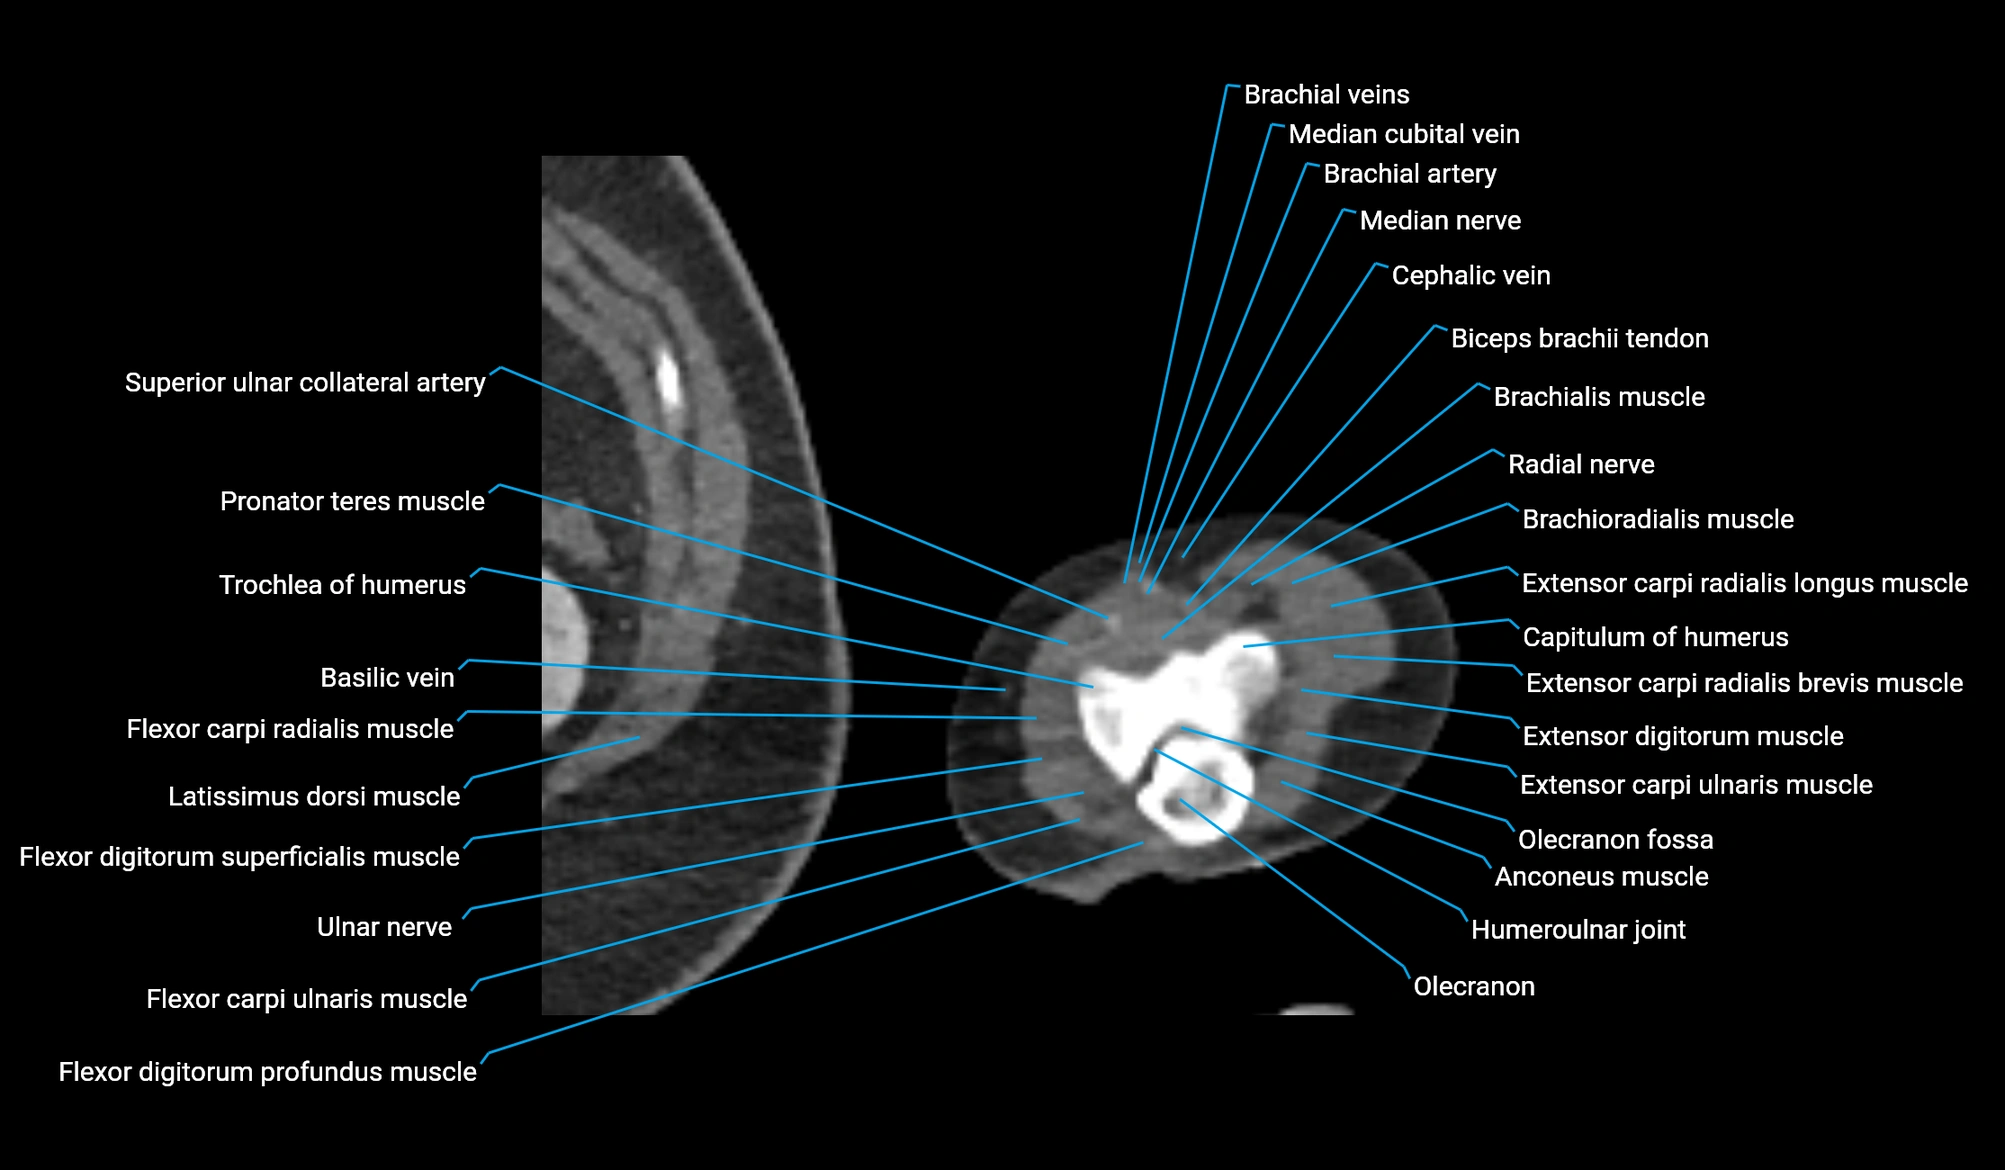

CT image